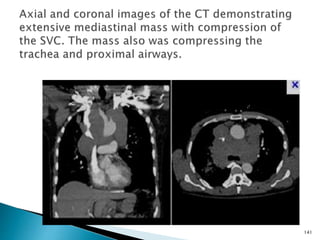

140

141